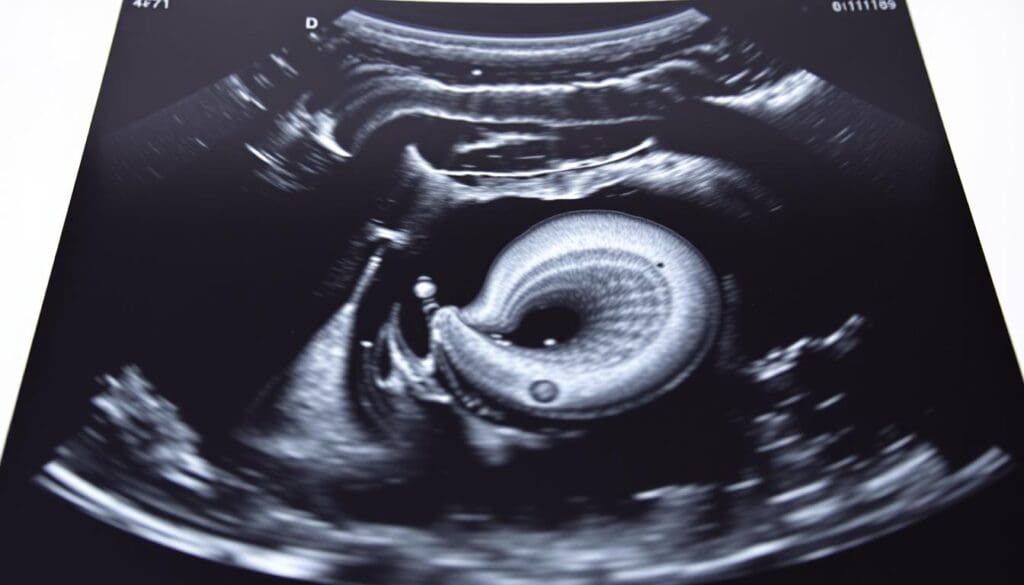

We use both transverse and longitudinal scans to see the aorta well. The transverse approach helps us check the aorta’s size and spot aneurysms. The longitudinal approach shows the aorta’s length and any issues like thrombi or wall problems.

To get accurate AAA results, it’s key to follow a set measurement plan. Measuring from outer wall to outer wall in both directions is vital. This helps in deciding the best treatment.

Outer Wall to Outer Wall Measurement Protocol

The outer wall to outer wall method is a top choice for AAA scans. It measures the aorta’s diameter from the outside of the front wall to the back wall. Being consistent in how you measure is important for getting reliable results.